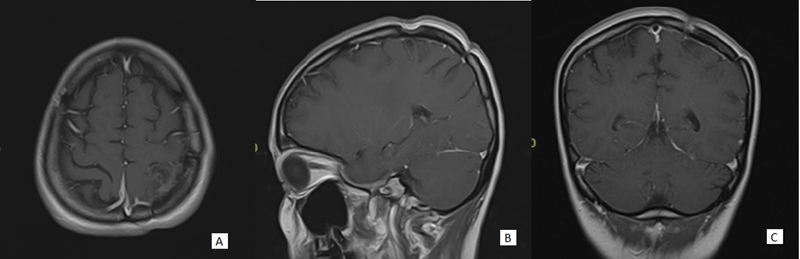

Objective  Meningiomas are the most common extra-axial tumors of the central nervous system. Meningiomas are particularly problematic when they invade deep or vital structures, causing the tumors to be inoperable. Nonsurgical adjunctive or salvage treatments to shrink a meningioma with multiple recurrences, located in deep-seated area or surgically unfit area, remain underexplored. The authors report a rare case of a spontaneously necrotic meningioma (World Health Organization [WHO] grade I) in a patient with systemic lupus erythematosus on chronic methotrexate and hydroxychloroquine. Case Study  A 29-year-old female with systemic lupus erythematosus had been treated with methotrexate and hydroxychloroquine for 7 years. She presented with episodes of seizures and hemiparesis. Neuroimaging revealed a possible necrotic meningioma in the left parietal parasagittal area. Subsequent intraoperative findings showed lytic tissue of the tumor, and by histopathology results the tumor was classified as WHO grade I with massive necrosis. After craniotomy with tumor removal, the patient's motor function fully recovered without recurrent seizures. Discussions  Necrotizing of small and benign meningioma is rarely found but otherwise interesting. The cause of this phenomenon is not yet understood thoroughly. In this case, we suspected various possible causes such as vasculitis interrupting blood supply, use of immunosuppressive drugs such as hydroxychloroquine or methotrexate, or, less likely, latent infections in the immunocompromised patient. Despite the lack of more evidence supports, this finding encourages further study of nonsurgical or salvage treatment of inoperable meningioma, so sequalae after refractory recurrences of meningioma can be prevented, and patient treatment outcomes can be improved.

Abstract Image